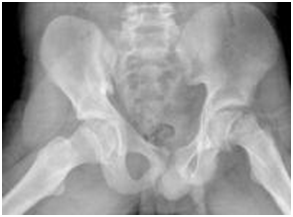

Physical examination revealed an adolescent boy with tall stature, exophthalmoses (Figure 1), anterior neck swelling. The swelling was diffuse, smooth, non-tender and moves with deglutition. Anthropometric measurements were weight 43.5kg (50th percentile), height 173cm (> 97th percentile) and body mass index 14.4kg/m2 (< 5th percentile). His pulse rate was 72/minute, regular and normal volume, blood pressure was 90/60mmHg and the heart sounds were normal without cardiac murmur. Examination of the left hip joint showed limited range of motion, particularly internal rotation. The right hip joint examination was unremarkable. He had an antalgic gait. His sexual maturity rating was Tanner stage 3. The radiographic findings confirmed left-sided slipped capital femoral epiphysis (Figure 2). Thyroid scan showed moderate enlargement of both lobes of the thyroid gland, with right slightly larger than the left. The thyroid lobes measured 2.1 x 5.1 x 2.1 and 2.2 x 3.2 x 1.6 cm, for right and left lobes, respectively. The parenchyma showed normal architectural and echo pattern with regularity of the outline. There was no evidence of invasion of adjacent blood vessels. The other laboratory findings are summarized in Table 1.

Figure 2 Radiograph showing left SCFE.

The diagnosis of Graves’ disease was based on typical clinical features (goiter, exophthalmoses) and elevated thyroid hormones (T3 and T4) and undetectable TSH. The diagnosis of slipped capital femoral epiphysis (SCFE) was suspected based on history of hip pain and limping in a tall, thin, pubertal adolescent boy and was subsequently confirmed by the radiographic findings. There was no radiographic evidence of fracture of the neck of left femur, thereby making fracture of the neck of the femur unlikely. Epidemiologically, Legg-Calve-Perthes’ disease (a vascular necrosis of the femoral head) is more common than SCFE but the typical age of presentation is 4 to 8 years.1 Our patient’s age (12 years) was outside this range. More importantly, the radiographic findings in our patient did not support Legg-Calve-Perthes’ disease. According to the report by Key,15 the chief differential points between SCFE and Legg-Calve-Perthes’ disease are age of the patient and the radiographic appearance.